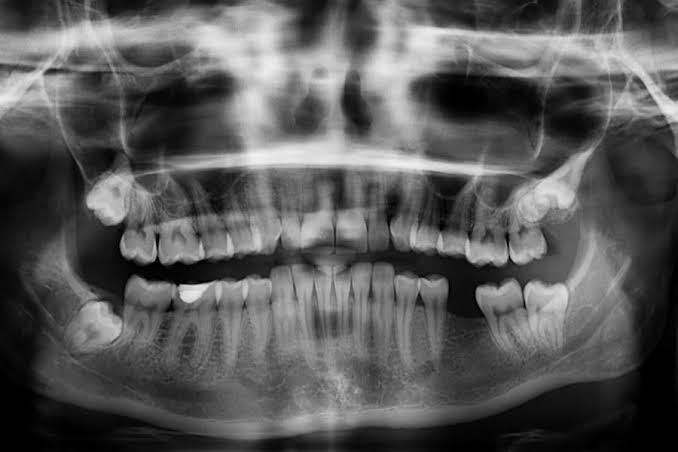

बनभलपुरा में पत्नी से हुए विवाद का गुस्सा पति ने अपने साले पर उतार दिया. जीजा के पिटाई में साले का जबड़ा टूट गया. साले ने जब अस्पताल पहुंचकर जबड़े का एक्सरे कराया तो जबड़ा टूटा हुआ निकला. साले की मां की तहरीर पर एसएसपी के निर्देश पर बनभूलपुरा पुलिस ने मुकदमा दर्ज कर जांच शुरू कर दी है.

जबड़ा टूटने के बाद बरेली में कराया इलाज: 24 जून को महिला का बेटा किसी काम से इंदिरानगर गया था, तभी उसके दामाद व उसके छोटे भाई ने बेटे के साथ मारपीट की. बेस अस्पताल में एक्सरे कराया तो जबड़ा टूटा पाया गया. इसके बाद महिला बेटे को उपचार के लिए राम मूर्ति अस्पताल बरेली ले गई. मामले की शिकायत पुलिस से की, लेकिन पुलिस ने गंभीरता से नहीं लिया. इसके बाद उसने इसकी शिकायत एसएसपी प्रह्लाद नारायण मीणा से की. एसएसपी के निर्देश पर बनभूलपुरा पुलिस ने मामला दर्ज कर लिया है. बनभूलपुरा थानाध्यक्ष नीरज भाकुनी ने बताया कि तहरीर के आधार पर आरोपी पर मारपीट, जानलेवा हमला व धमकी देने की धारा में मुकदमा दर्ज किया गया है. आगे की कार्रवाई की जा रही है.